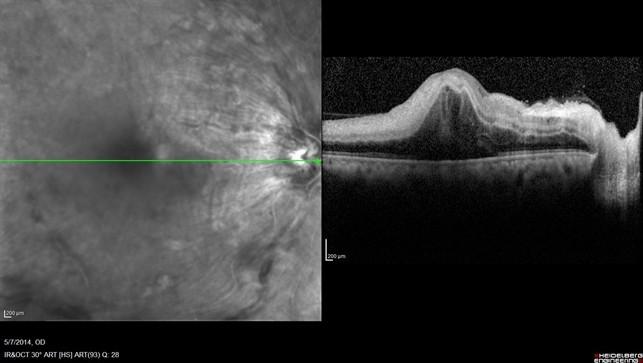

ОКТ сетчатки

Режим «картирования» позволяет оценить толщину нейросенсорной сетчатки макулярной зоны. Метод используется для диагностики, динамического наблюдения и оценки эффективности лечения заболеваний сетчатки. При окклюзии вен сетчатки ОКТ позволяет:

- определить высоту и площадь макулярного отека;

- определить структурные характеристики отека (кистозные изменения, отслойка нейроэпителия);

- выявить наличие витреоретинальных тракций;

- выявить наличие эпиретинального фиброза;

- определить положение задней гиалоидной мембраны стекловидного тела;

- наблюдать за эффективностью лечения макулярного отека.